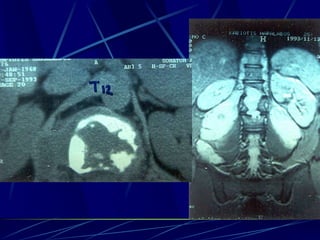

Infections of the spine

Echinococcus

Φυματίωση της σπονδυλικής στήλης